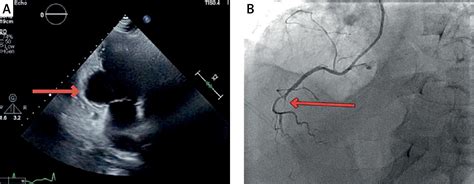

• Echocardiogram: This uses sound waves to create images of the heart, allowing doctors to visualize the aneurysm and assess its size and location.

• Cardiac Catheterization: This invasive procedure involves inserting a catheter into the heart to measure pressure and blood flow, and to visualize the coronary arteries.

Diagnosing a Left Ventricular Aneurysm involves a combination of medical history, physical examination, and various diagnostic tests. Some of the key diagnostic methods include: